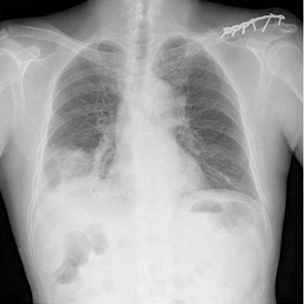

IgG4関連疾患の胸部レントゲン(X-p)

gG4関連疾患の胸部レントゲン写真には、リンパ節腫大(縦隔リンパ節の腫脹)や、肺野の「すりガラス影」、「結節影」、「線維化」といった多彩な陰影が見られます。また…

肺紋理がしっかり見えるということは、肺血管の肥大、気管支炎の炎症などが考えられます。合わせてどのような所見があるかも非常に重要になります。 このレントゲン写真で…